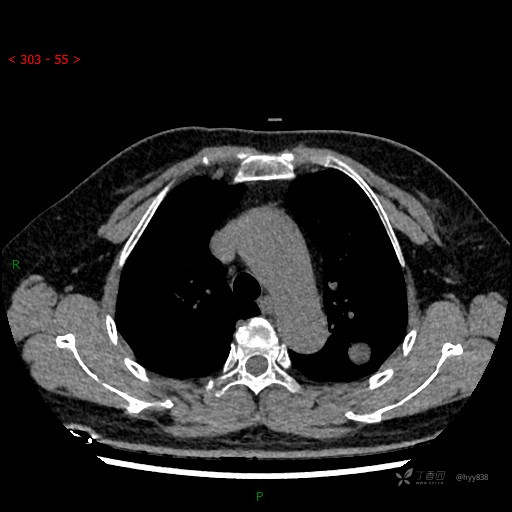

增强动脉期

各期CT值:28hu、58hu、69hu